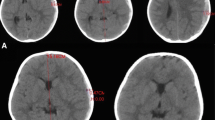

Initial whole blood count, liver function tests, renal function tests, clotting profile and basic investigations were normal. X-ray of the thoracolumbar spine did not reveal any abnormality. Non-contrast CT brain showed bilateral acute on chronic SDH. Left sided SDH was over the frontal, parietal, occipital lobes and right-sided SDH was located over the parietal and occipital lobes (Fig 1). The SDH extended into the interhemispheric space at the vertex but was not seen in the deeper part of the brain. There were no intracranial hemorrhages. Because the left sided SDH was larger there was a mild midline shift and subfalcine herniation to the right side.

Non-contrast computer tomography of the brain showing bilateral acute on chronic sub dural hematoma. Left sided sub dural hematoma was over the frontal, parietal, occipital lobes and right-sided sub dural hematoma was located over the parietal and occipital lobes. The sub dural hematoma extended into the interhemispheric space at the vertex but was not seen in the deeper part of the brain. The left sided sub dural hematoma was larger and there was a mild midline shift and subfalcine herniation to the right side